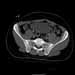

25 yo brittle diabetic, became hypoglycemic and passed out on his motorcycle. Sustained bilateral lateral Hoffa fractures with associated LCL injury on the right and right distal radius fracture. I have questions regarding his pelvic ring/acetabular fracture on the left. Appears to be a very low posterior column fracture with associated posterior wall, marginal impaction. Superior and inferior rami fractures as well on the left giving him a floating segment of inf ramus/ischium/posterior column, but no detectable posterior ring injury. Should the posterior column/posterior wall fracture be addressed surgically because of the marginal impaction? Or is this fracture low enough to be treated non-operatively? I appreciate the input.

It's an interesting case. The plain films show the impaction, but most of the joint looks pretty good. The CT cuts look awful, though.

The impaction is so big I don't think I would ignore it. It IS down low, but it takes up almost the whole southern hemisphere of his joint.